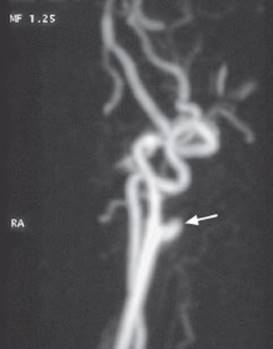

Fig. 4.27 Color-coded duplex ultrasonography of an occlusion of the left internal carotid a. 3 cm above the carotid bifurcation. a Blood flow can be seen up to the bifurcation. In the internal carotid a. (ICALT), there is only minimal movement of the blood column. b Doppler ultrasonography reveals no more than a brief forward flow in early systole at greatly reduced maximal speed; backward flow is already seen in early diastole.

Fig. 4.27 c MR angiography reveals occlusion of the internal carotid artery.

Indications. The velocity and flow profile (laminar or turbulent) of the blood flowing within a particular vessel depend, among other things, on the vessel's caliber and on the nature of its wall. Ultrasound studies aid in the detection of vascular stenosis and occlusion, vessel wall irregularities, abnormalities of the speed and direction of blood flow, and turbulent flow. Insonation of the extra- and intracranial vessels (e.g., of the middle cerebral a. through the thin bone of the “temporal window,” or of the basilar a. through the foramen magnum) yields an informative picture of the current state of blood flow in the brain (Fig. 4.27). This diagnostic technique is inexpensive, non-invasive, and free of risk.